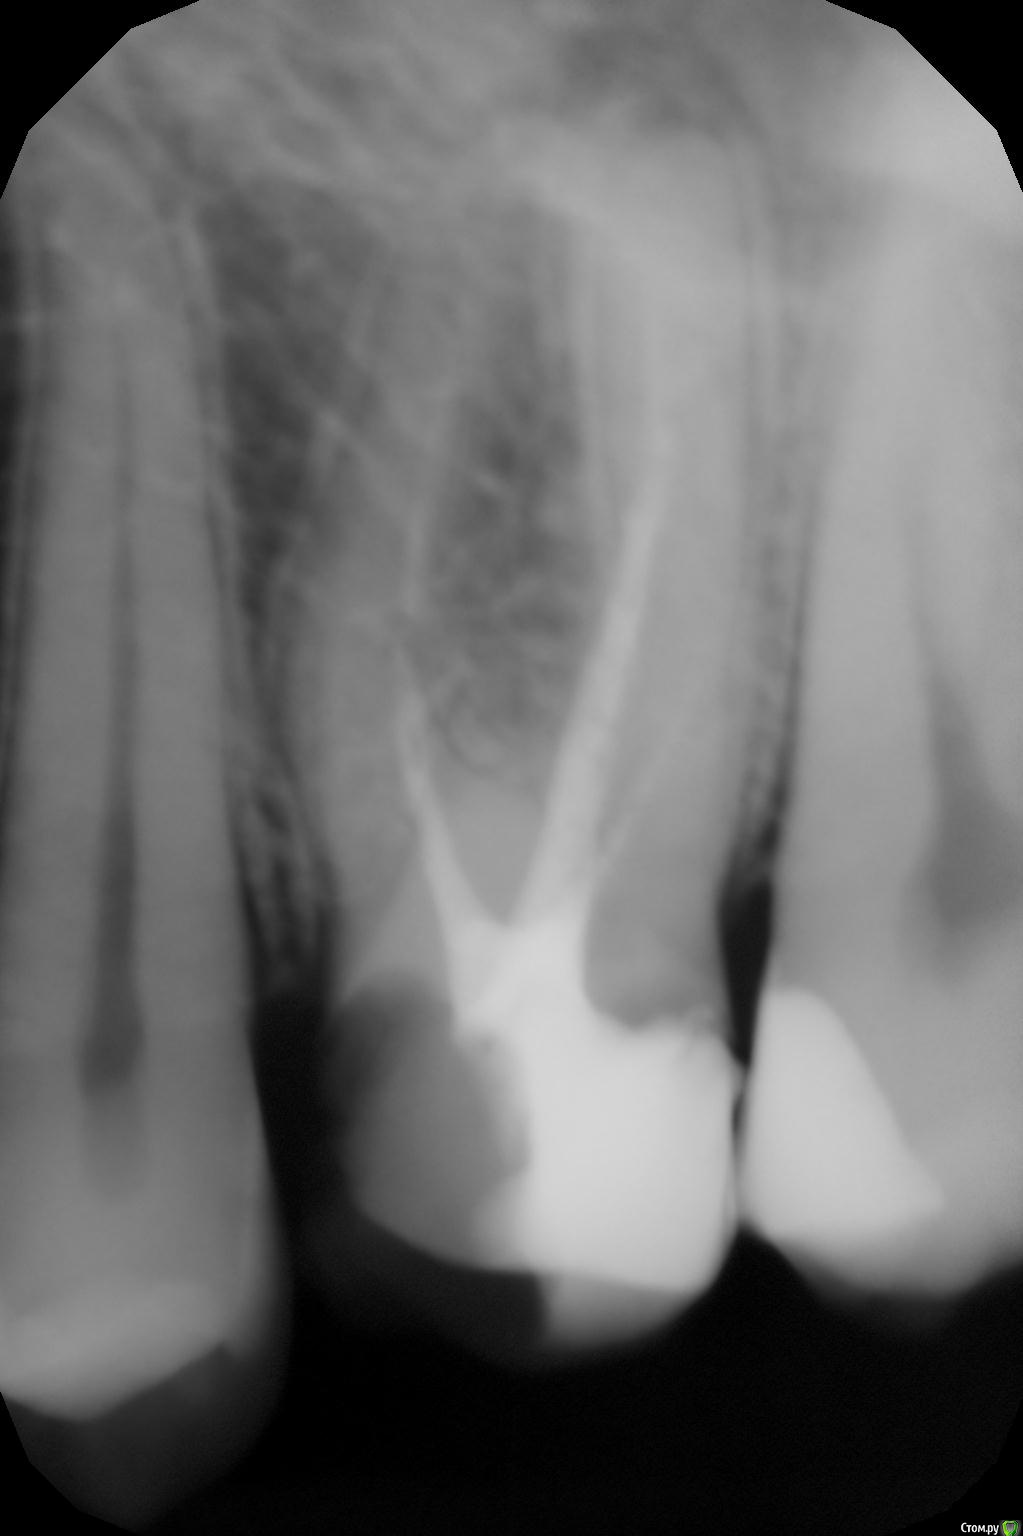

Banana Опубликовано 18 августа, 2016 Поделиться Опубликовано 18 августа, 2016 (изменено) Всем здоровья! Впервые столкнулся со стоматологическими проблемами на таком серьёзном уровне, и хотелось бы услышать мнение специалистов по поводу состояния моего зуба и того, что мне предстоит.Итак, проблема с верхней шестёркой. Анамнез. Давным-давно возник кариес, дорос до пульпита. Давным-давно обратился в государственную поликлинику. Там кариес вычистили, удалили нерв, в ходе прохождения одного из каналов допустили перфорацию, залили резорцином, сверху поставили уродливую и не функциональную светозатвердевающую пломбу. С ней я жил не тужил годы, пока не обратился за чисткой зубов в одну коммерческую клинику. Там настояли, чтобы я дал им снять пломбу, и показали, какая кошмарная чернота была под ней. Почистили, полечили. Тогда же стали проходить каналы, но прошли только три из четырёх, потому что перфорация и резорцин. К тому моменту от зуба выше десны оставались только две стеночки, и они предложили два варианта: коронка, но без всяких гарантий, что она хоть сколько-то простоит, и удаление -> синус-лифтинг -> имплантация. Про синус-лифнтинг уклончиво сказали, что по данным не ясно, понадобится ли он, и это будет видно только в ходе операции имплантации 8-мм импланта. Я выбрал последнее, поскольку это более долговечное решение проблемы. Финансовый план лечения такой:1.1 Анестезия аппликационная1.2 Анестезия инфильтрационная, проводниковая1.3 Удаление зуба сложное1.4. Закрытый синус-лифтинг (включая Bio-oss 0,25, PRP и забор материала для него)1.5. Имплантация CSM, установка формирователя десны2.1 Индивидуальная ложка2.2 Двухслойный слепок с одной челюсти (силиконовая маска)3.1 Коронка с трансокклюзией на имплант На снимках зуб до лечения и после того, как прошли три канала. На rghost выложил КТ (пароль Banana): http://rgho.st/private/8fXPD8WRy/698183a50e52bbba6e608a26d74e9344 Вопросы достопочтенной аудитории:1. Обосновано ли в данном случае удаление зуба?2. Насколько обоснован закрытый синус-лифтинг?3. Достаточно ли кости для того, чтобы провести имплантацию сразу после удаления, как и запланировано?4. К чему мне готовиться? Насколько всё плохо выглядит по снимкам? Правда ли, что после операции придётся на время исключить твёрдую пищу?5. Буду ли я играть на пианино? Всем добра! Изменено 18 августа, 2016 пользователем Banana Ссылка на комментарий

Banana Опубликовано 20 августа, 2016 Автор Поделиться Опубликовано 20 августа, 2016 Здравствуйте. КТ есть?Да, и ссылка на него есть в посте. Но уже всё: зуб удалили по частям, при удалении - перфорация мембраны Шнайдера, поэтому отказались от синус-лифтинга и зашили с PRP. Через неделю снимут швы, через два месяца снова КТ, и далее определятся, возможен ли ещё закрытый синус-лифтинг. Ссылка на комментарий